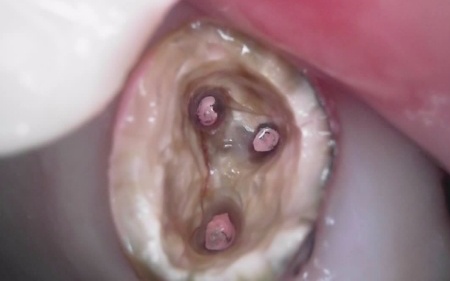

痛みが出ているブリッジ周辺の治療として、ブリッジの土台となっていて、歯根が割れている手前の歯(第2小臼歯)は抜き、根尖病巣を発症している奥の歯(第2大臼歯)は、根管治療を行います。

根管治療とは、感染した神経を取り除いて、歯根内部を清掃・消毒する治療方法のことです。